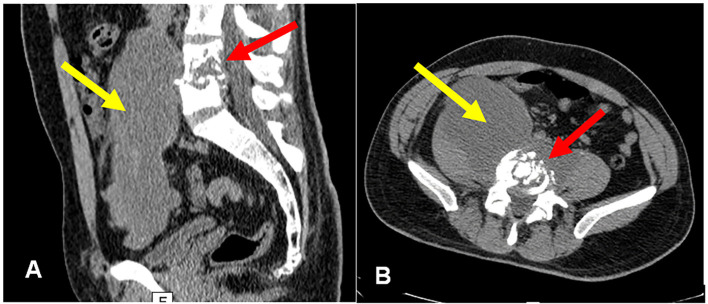

Psoas muscle abscess is an insidious disease, with varied clinical manifestations and a challenging diagnosis. This pathology has been more frequently identified due to the increased availability of high-quality radiological imaging, such as computed tomography. In Brazil, Mycobacterium tuberculosis is the most common secondary etiologic agent of psoas abscess. We report the case of a 28-year-old immunocompetent man diagnosed with disseminated tuberculosis, affecting the lungs, lumbar spine, and psoas muscle, leading to permanent locomotion sequelae. This case is very relevant for osteoarticular complaints, as low back pain and limping were the initial symptoms. Diagnosis was confirmed by ultrasound-guided percutaneous drainage of the psoas muscle abscess and detection of the M. tuberculosis complex via Xpert MTB/RIF. A 12-month treatment with antitubercular drugs was effective.